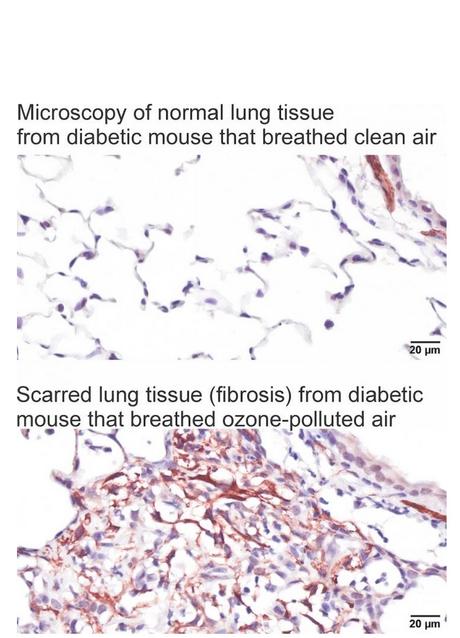

L’étude, menée sur des souris en bonne santé, des souris présentant une résistance à l'insuline légère et des souris présentant une résistance à l'insuline sévère, confirme

- une relation directe entre les niveaux de résistance à l'insuline et la gravité de l'inflammation et de la fibrose pulmonaires ;

- les souris diabétiques se montrent particulièrement sensibles à l'inflammation et au remodelage tissulaire causé par une exposition répétée à l'ozone.

Ces données, chez l’animal, confirment que l'exposition à l'ozone pourrait exacerber la fibrose pulmonaire, en particulier chez les personnes diabétiques et un diabète mal contrôlé, peut aggraver des lésions pulmonaires.